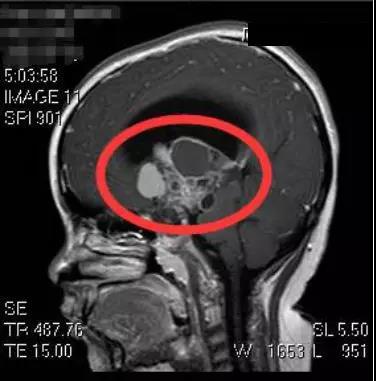

为进一步诊治,刘女士带着小明来到广东三九脑科医院就医。该院副院长、神经外五科主任鲁明为小明查体后发现,小明体型肥胖、身高偏矮,头颅磁共振检查提示鞍区占位性病变,结合其它临床症状及相关检查,考虑为颅咽管瘤。

5月22日,鲁明为小明在全麻下行巨大颅咽管瘤切除术。术中发现肿瘤巨大,包裹了颈内动脉、大脑前动脉和中动脉,且肿瘤位于脑深部,钙化明显,质地坚韧,手术难度极大。经过手术团队近12个小时的奋战,才终于顺利将肿瘤切除。术后测量显示该颅咽管瘤大小约5cm×5.6cm×7.7cm厘米,比鸡蛋还大。目前小明恢复良好。